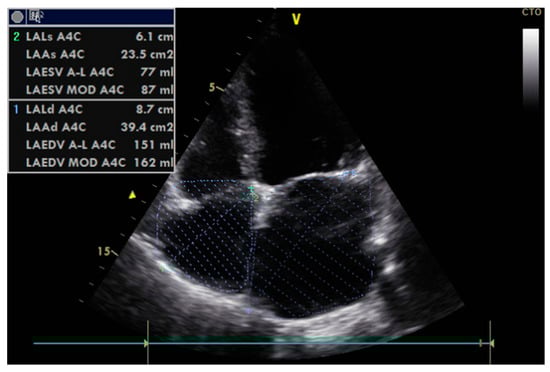

- Left atrial size assessed by area or better by left atrium volume (indexed) (LAVi; Figure 7).